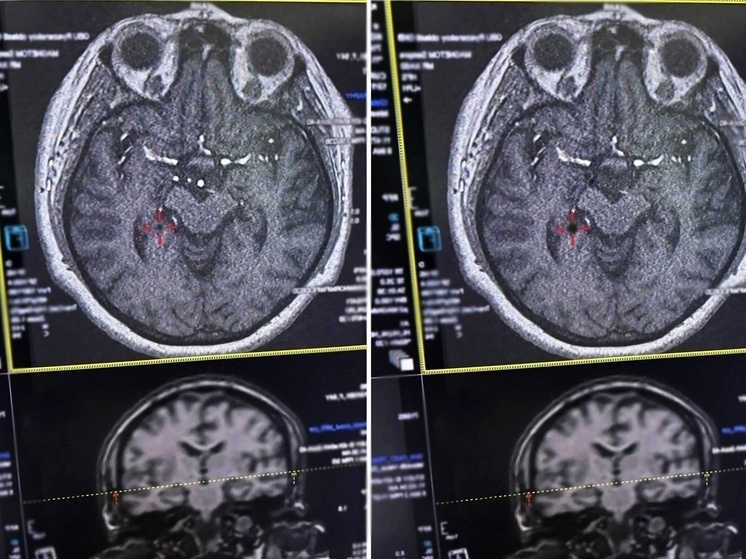

В Рязанской области врачи областной клинической больницы спасли жизнь женщине, у которой случился инсульт. Об этом сообщили 13 января в социальных сетях регионального Минздрава. Пациентке стало плохо, когда она находилась в магазине вместе с дочерью. Женщина почувствовала резкое головокружение, после чего потеряла сознание. По её словам, дочь удерживала её голову и звала на помощь, прося вызвать скорую помощь. Во время госпитализации у пострадавшей была парализована правая часть тела, а также наблюдалась выраженная головная боль. Как уточнили в Министерстве здравоохранения, бригада врачей оперативно начала лечение в первые четыре с половиной часа после приступа, что критически важно при инсульте. Медикам удалось провести тромболизис — процедуру по растворению тромба с помощью специальных препаратов. Именно своевременное вмешательство помогло стабилизировать состояние женщины.